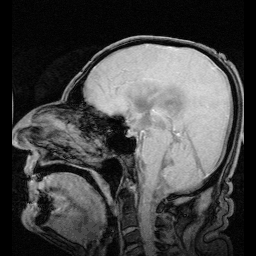

Ventricular system

In neuroanatomy, the ventricular system is a set of four interconnected cavities known as cerebral ventricles in the brain.[1][2] Within each ventricle is a region of choroid plexus which produces the circulating cerebrospinal fluid (CSF). The ventricular system is continuous with the central canal of the spinal cord from the fourth ventricle,[3] allowing for the flow of CSF to circulate.[3][4]

The system comprises four ventricles:[5]

- lateral ventricles right and left (one for each hemisphere)

- third ventricle

- fourth ventricle

There are several foramina, openings acting as channels, that connect the ventricles. The interventricular foramina (also called the foramina of Monro) connect the lateral ventricles to the third ventricle through which the cerebrospinal fluid can flow.

Ventricles

The four cavities of the human brain are called ventricles.[6] The two largest are the lateral ventricles in the cerebrum, the third ventricle is in the diencephalon of the forebrain between the right and left thalamus, and the fourth ventricle is located at the back of the pons and upper half of the medulla oblongata of the hindbrain. The ventricles are concerned with the production and circulation of cerebrospinal fluid.[7]